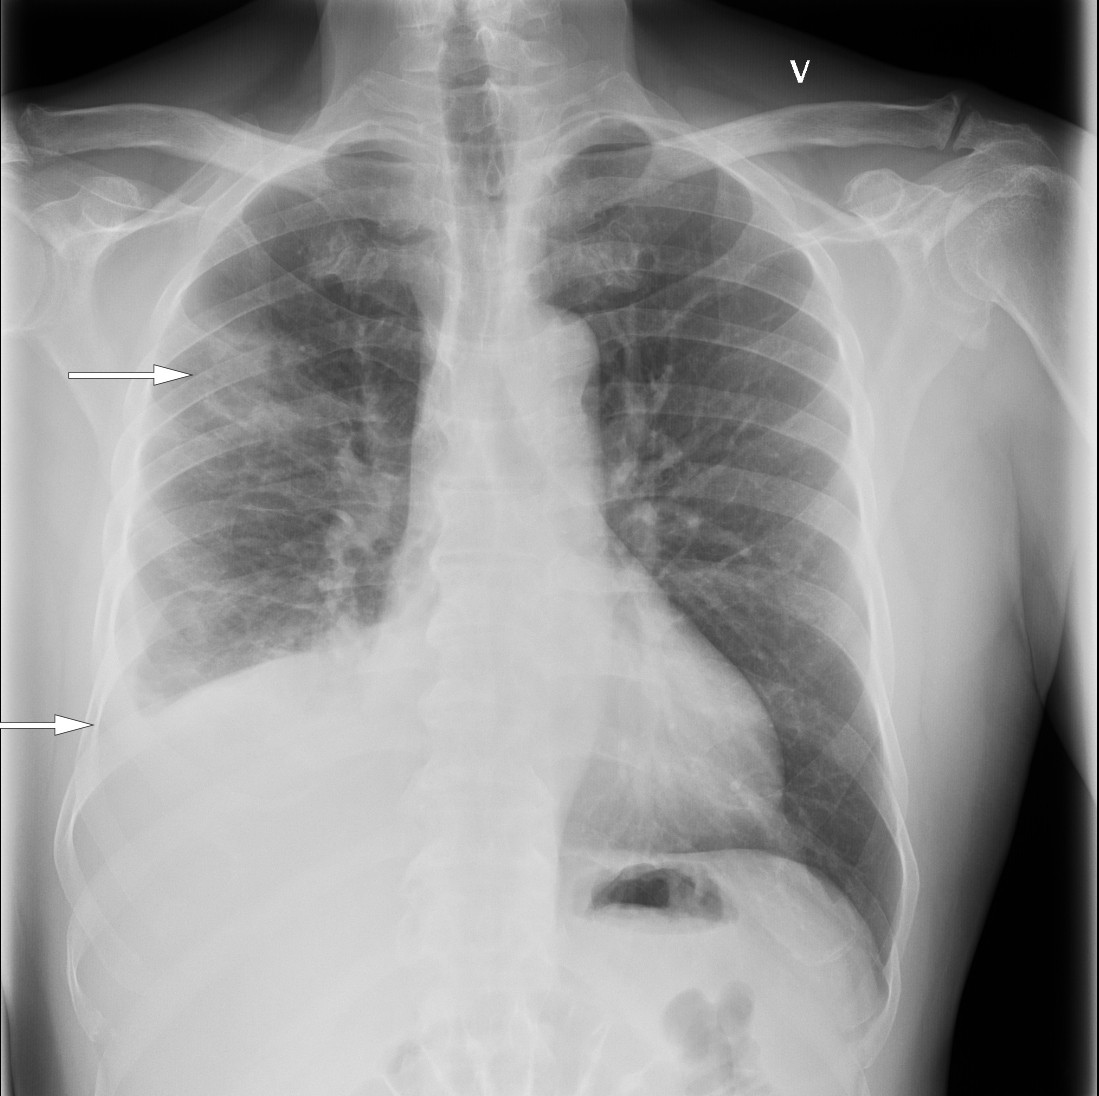

På sykehuset var allmenntilstanden god. Blodtrykket var 168/84 mm Hg, puls 85 slag per minutt, temperatur 37,8 °C i øret, perifer oksygenmetning 97 % i romluft og respirasjonsfrekvens 20 per minutt. Han hadde en systolisk bilyd grad 1 over hjertet, best hørbar i andre høyre interkostalrom, og basalt over høyre lunge var det svekket respirasjonslyd med perkutatorisk dempning. Han hadde ingen cyanose, lymfeknutesvulst, fortykkelse av fingre og tær (clubbing), urglassnegler, palpabel hepatosplenomegali, eksantemer eller perifere ødemer. Blodprøvene viste CRP 105 mg/L og albumin 34,4 g/L (35–45 g/L). Hematologiske prøver, elektrolytter, nyre-, lever- og galleprøver var alle innenfor normale grenser. Røntgen thorax (figur 1) viste flere delvis konsoliderte fortetninger, særlig i nedre del av høyre lunges overlapp, atelektasestriper og høyresidig pleuravæske. Mengden var for liten for drenasje. Basert på sykehistorien med tørrhoste, pneumonisuspekte fortetninger på lungerøntgen og moderat forhøyet CRP uten leukocytose, ble tilstanden oppfattet som en atypisk pneumoni. Pasienten ble utskrevet etter ett døgn med azitromycintabletter 500 mg daglig i tre dager. Azitromycin ble valgt til fordel for erytromycin på grunn av økt intracellulær konsentrasjon, økt sannsynlighet for etterlevelse og erfaringsmessig mindre sannsynlighet for gastrointestinale bivirkninger.

I siste nummer av Tidsskriftet blir det presentert en bemerkelsesverdig publikasjon om en mann i 50 års alderen med utenlandsk opprinnelse. Han tok kontakt med sin fastlege på grunn av tørrhoste og med residiverende feber. Etter påfølgende henvisning til i det lokale sykehus ble det ved røntgenundersøkelse påvist infiltrater i høyre lunges overlapp og høyresidig plevravæske.